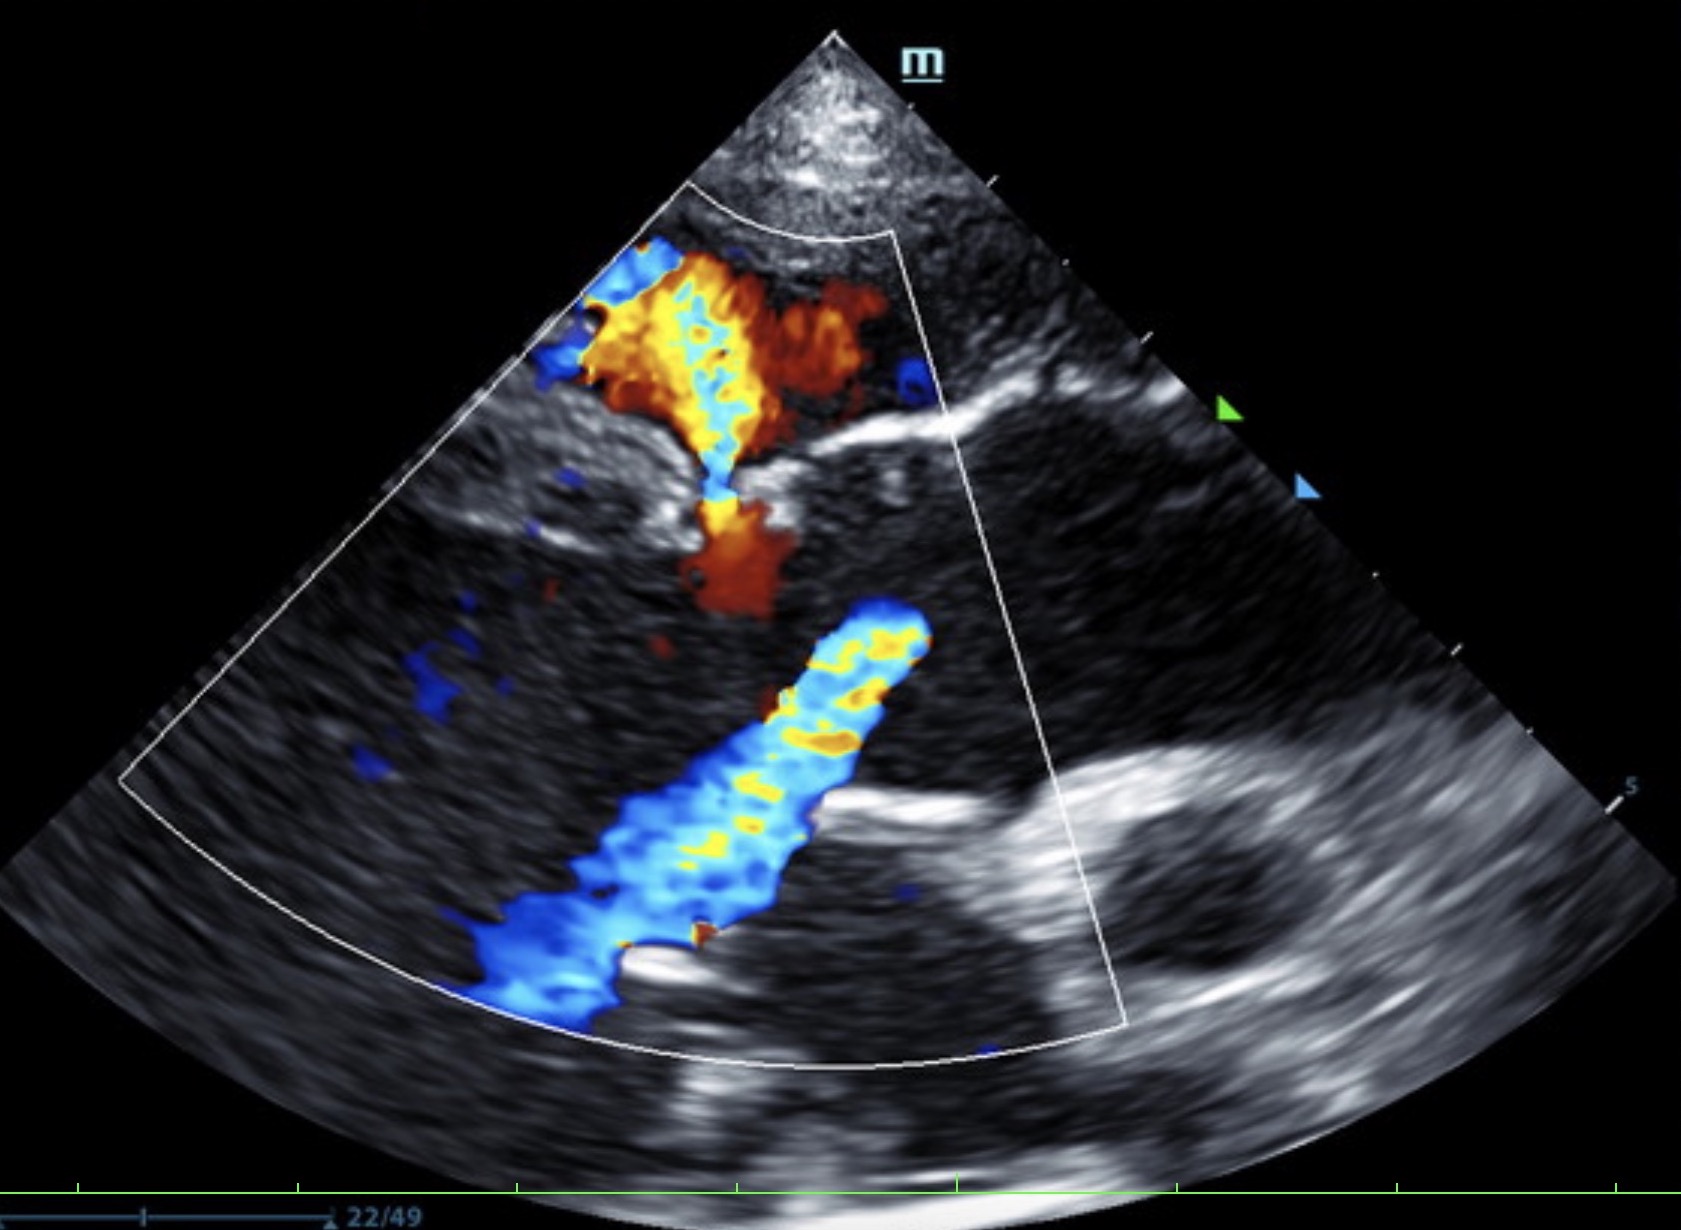

Our experienced SDEP® certified technicians, Kelly Reschny, RVT & Crystal Hill, RVT will come to your clinic and perform a diagnostic ultrasound on your patient. The images will then be submitted to a SonoPath specialist who will provide a comprehensive report. The report will include sonographic findings, internal medicine diagnostics and treatment recommendations with annotated images identifying any pathology or areas of concern. If needed, our technicians can perform ultrasound-guided fine needle aspirates, abdominocentesis or pericardiocentesis.

The Focal Zone fueled by Sonopath, a mobile veterinary ultrasound service, gives you a sneak peek on its monthly Star Cases.

VSD, CHF, and Thoracic Mass In A 4-Year-Old Intact Male Sphynx Cat: Our 2023 Star…

Retrobulbar Mass – Right Eye In A 4-Year-Old, MN, English Setter: Our 2023 Star Cases